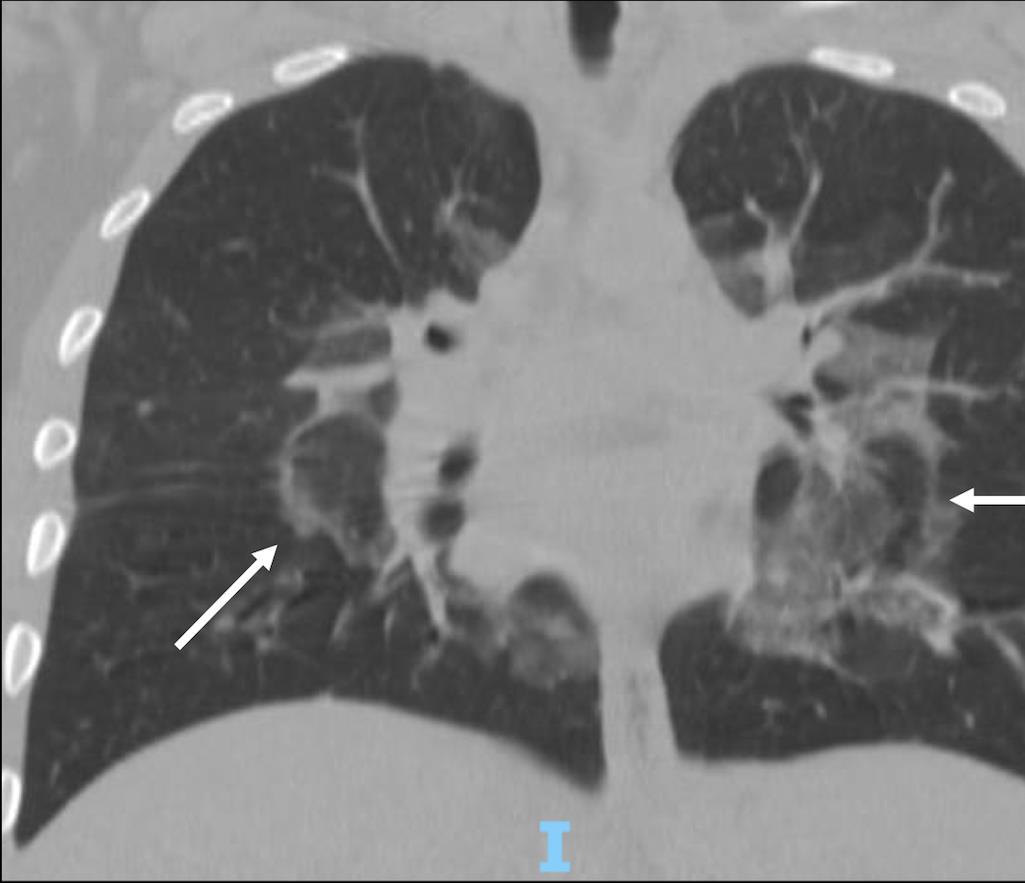

Acute Pediatric COVID-19: CT

21 Imaging of Covid 19 infection in children

3 Phases

Early: "Halo" sign

Local infection

Progressive: Diffuse GGO

Developed: Consolidation

Surr vasc congestion

Inflammation - adj alveoli

Alveoli fill with fluid/cells

Local infection Surr vasc congestion